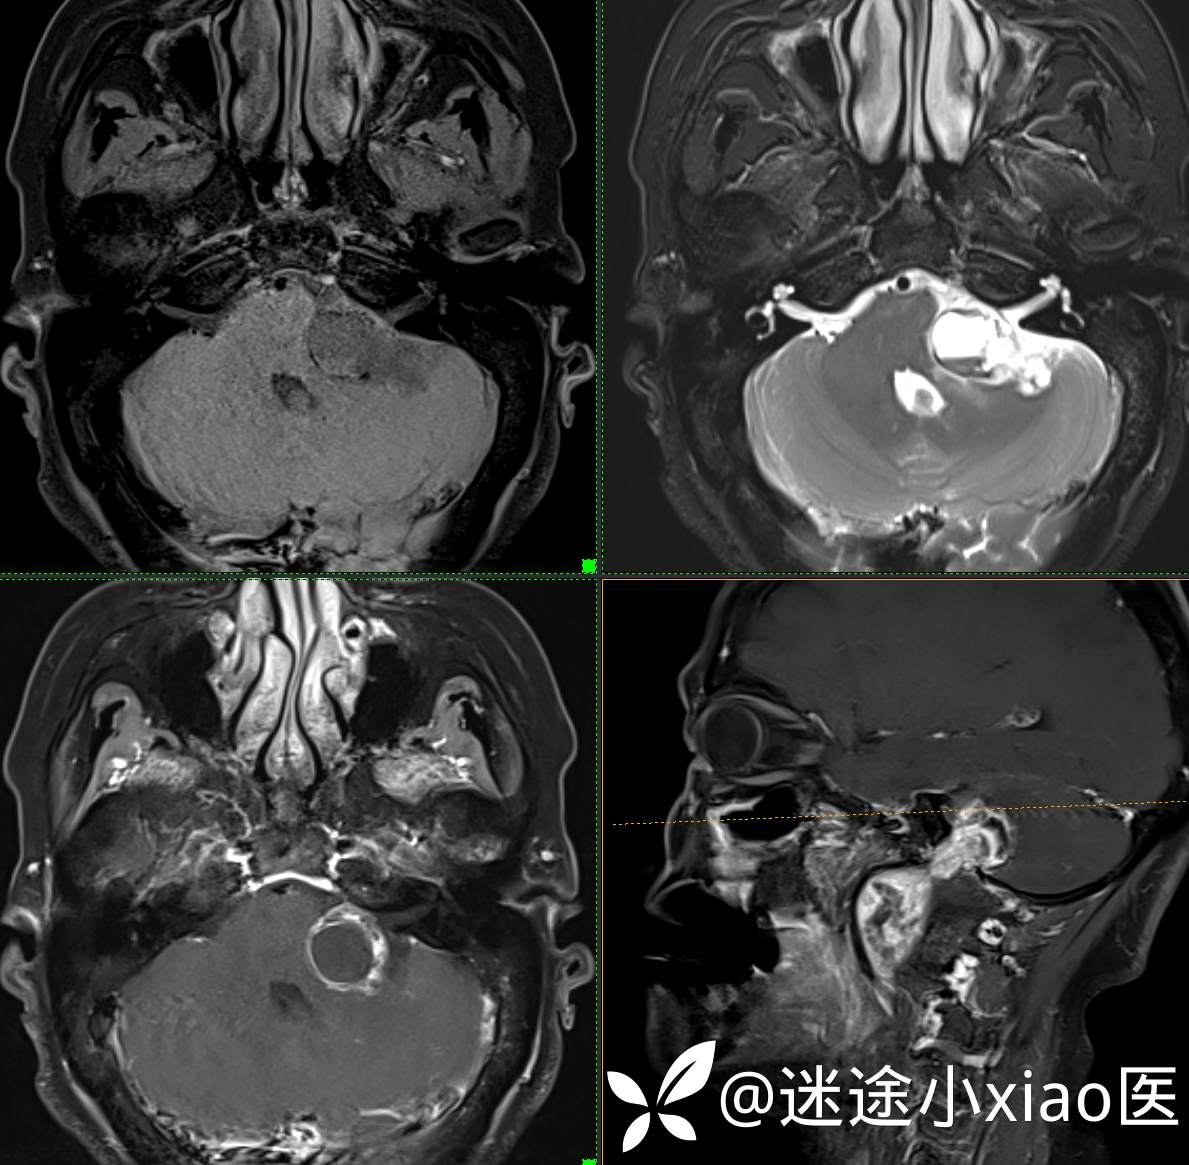

头颈组17:颈静脉孔区占位,副神经节瘤?神经鞘瘤?脑膜瘤?

患者性别:女

患者年龄:57岁

主 诉:  声音嘶哑进食困难伴左侧颌部麻木半年

现病史:  【患者半年前无明显诱因出现声音嘶哑,进食困难,只能进食糊状食物,伴有恶心呕吐,无明显头痛头晕,未加重视。